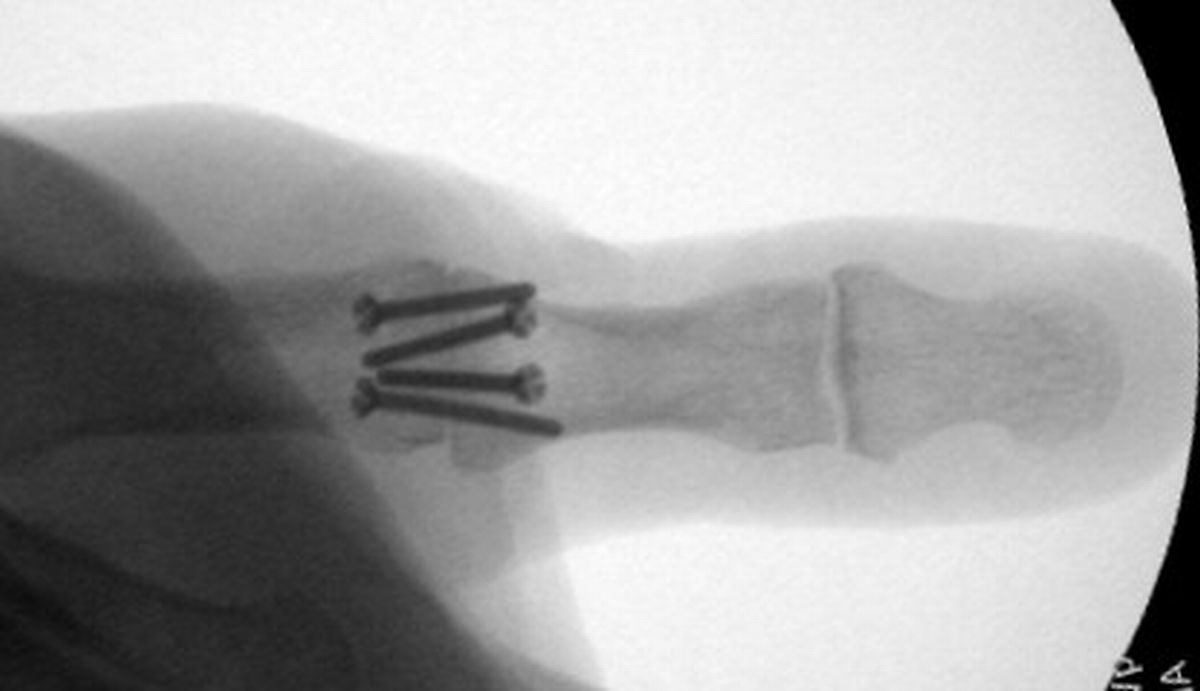

| Smaller plates and screws

from the Lorenz craniofacial fixation system were used for this MCP

fusion. |

| Low profile, but possibly

too small in terms of rigidity. Despite this concern, the patient did

well. |

| In this case, 0.045"

K-wires were used for provisional fixation: |

| These were then replaced,

one at a time, with 1.5mm screws. Because of the entry angles, the

countersink bit was used to reduce screw head prominence. |